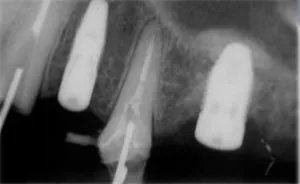

Quando perdemos dentes na região posterior de maxila (região superior na parte de trás do arco dentário), com o passar do tempo pode ocorrer perda de grande quantidade de osso em altura e assim nos aproximamos de uma região chamada de seio maxilar.

O seio maxilar é uma cavidade em nossa face que tem diversas funções, muito associada a respiração.

Ao seu redor encontramos uma fina membrana. Essa membrana pode ser elevada para a colocação do enxerto ósseo, após isso, esperamos o tempo necessário para a consolidação do osso e colocação do implante.

Ela envolve completamente a cavidade do seio maxilar. A partir do levantamento dela, conseguimos criar um "espaço“ para a colocação do enxerto ósseo.

1 - O primeiro é quando ainda temos uma pequena quantidade de osso remanescente, assim podemos realizar a cirurgia de levantamento do seio maxilar e no mesmo ato cirúrgico instalar o implante. Após isso, esperamos em média 6 meses para colocar um dente sobre o implante.

2 - O segundo, acontece quando temos praticamente nenhum osso remanescente. Portanto só podemos realizar a cirurgia de levantamento do seio maxilar sem a instalação do implante. Devemos esperar 6 meses para colocar os implantes e mais 4 a 6 meses para poder colocar um dentes sobre o implante.